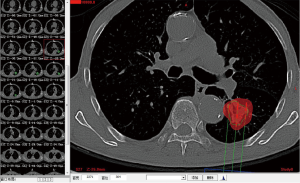

Complete blood cell count, full panel of coagulation function, and ECG were performed routinely for all the patients prior to the operation. A pulmonary plain + contrast-enhanced CT scan was performed to observe the tumor and its blood supply carefully. Three-dimensional treatment planning system (TPS) software was used to calculate the therapeutic dose, amount, spacing and distribution of seeds in the therapeutic target area and adjacent tissues. The amount of particle required for implantation was determined by the following formula: (tumor length + tumor width + tumor height)/3(cm)×5/activity per particle (mCi). The preoperative planning and dose volume histogram (DVH) were completed (Figures 1,2). Prior to the operation, the patients were informed of the course of operation, signed the informed consent form, and instructed to do breathing exercises.

As illustrated in Table 3, tumors were significantly reduced in all 6 patients after the implantation of radioactive particles. A typical case can be seen in Figures 4,5.

As shown in Figure 7 and Figure 3, there were 2 CRs and 4 PRs after follow-up for 1 month, indicating a response rate (RR) of 6/6, and a disease control rate (DCR) of 6/6; six patients were followed up for 6 months, including one patient who refused follow-up visit (still alive),while the other 5 patients were followed up regularly, including 3 CRs and 2 PRs; five patients were followed up for 12 months, including 3 CRs, 1 PR and 1 PD, indicating an RR of 4/5, a DCR of 4/5, and a progression rate of 1/5; four patients were followed up for 18 months, including 3 CRs and 1 SD, indicating a RR of 3/4 and a DCR of 4/4; four patients were followed up for 24 months, including 1 patient who refused a follow-up visit (still alive), while the other 3 patients were still followed up regularly; there were still 4 patients who were followed up for 30 months, including 1 patient who refused follow-up visit (alive) and 3 patients who were followed up on a regular basis; one patient was followed up for 36 months and had a recurrence of primary lesion, with the response being evaluated as PD. In addition, Figure 7 shows that patient E achieved significant response after implantation of 125I particles, and the response was evaluated as CR 1 month after implantation (Figures 8,9); however, the primary lesion recurred and was enlarged with left lung metastasis in month 12 (Figures 10,11), whereupon the response was evaluated as PD. The patient was given CT-guided implantation of 125I radioactive particles again for treatment of the recurrent lesion. The repeated pulmonary CT after re-implantation showed significant reduction of tumor (reduction rate 27.32%), as shown in Figure 12, and the response was subsequently re-evaluated as SD.

Other relevant studies have shown a unique advantage of implantation of radioactive particles in the treatment of lung cancer. In a study by Lu et al. (10), 15 patients with obstructive pneumonia caused by central type lung cancer were given a bronchoscopic implantation of 125I radioactive particles, and followed up in months 2, 6, 12, 18 and 24 after implantation. The median survival was 15.6 months, and the one-year lung recruitment rate was 80.0%, which significantly improved the quality of life. To compare, in our study’s response evaluation from regular follow-up of patients who received the CT-guided implantation of radioactive 125I, it was found that the tumors had significantly shrunk in all 6 patients. Typical cases are illustrated in Figures 4 and 5, and as can be seen in Figure 6, the most obvious reduction of tumor was seen in the 6th month of follow-up. In the 5 patients who were followed up, there were 3 CRs, indicating an RR of 5/5 (100%) and a DCR of 5/5 (100%). This shows that the implantation of radioactive particle achieved the best response within 6 months in the treatment of early lung cancer. In addition, as Figure 3 shows, 5 patients were followed up 1 year after implantation and had a survival rate of 5/5 (100%), 4 patients were followed up 2 years after implantation and had a survival rate of 4/4 (100%), and the longest time after enrollment was up to 3 years and 5 months; at the time of writing, this patient is still alive. The observations above demonstrate the significant efficacy of the implantation of 125I radioactive particles in treatment of early lung cancer.